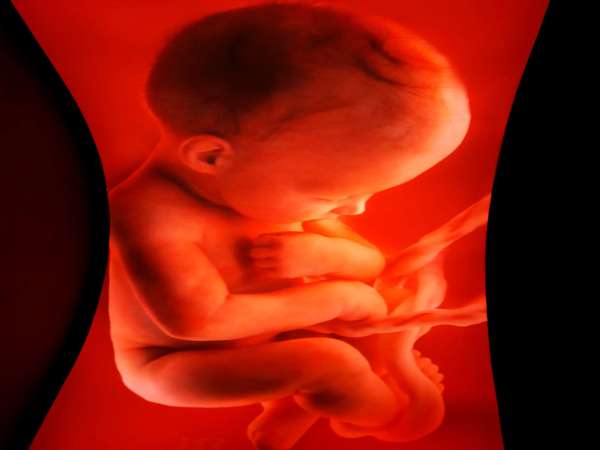

படிப்படியான வளர்ச்சி!

நாமும் இந்த மாதிரி ஒரு வடிவத்தில் இருந்து தான் இன்று இவ்வாறு வளர்ந்து இருக்கிறோம் என்பதை நினைவில் நிறுத்தவும். குழந்தைகள் சரியான வளர்ச்சி மற்றும் வடிவம் பெற்ற பின், அவர்கள் சாதாரண மனித உருவங்களை போல காட்சி அளிப்பர். மனிதர்களின் வளர்ச்சி என்பதை படிப்படியாக நிகழக்கூடியது தான்; குழந்தை கருவில் உருவான பின் ஏற்படும் வளர்ச்சியும் சரி, பிறந்த பின் ஏற்படும் வளர்ச்சியும் சரி. மெதுவானதாக, படிப்படியானதாக இருக்கும்.

குழந்தைகளை சரியாக ஸ்கேன் பரிசோதனைகளின் பொழுது காண முடியவில்லை என்றால் பெற்றோர் பயம் கொள்ள தேவையில்லை; அதே போல் குழந்தைகளின் உடல் உறுப்புகளில் ஏதேனும் குறைகளை கண்டாலும் பெற்றோர் மனம் தளராமல் வரவிருக்கும் தங்கள் வாரிசிற்கு வசந்தமான எதிர்காலத்தினை எப்படி அமைத்து கொடுப்பது என்பது பற்றி தான் சிந்திக்க வேண்டும்.

நடப்பது எதுவாயினும் நன்மைக்கே என்ற எண்ணத்தில் கருவில் உருவான குழந்தையை பெற்று எடுத்து முழு அன்பு மற்றும் பாசம் காட்டி வளர்த்து, சிறந்த பெற்றோராக இருக்க முயலுங்கள்..!